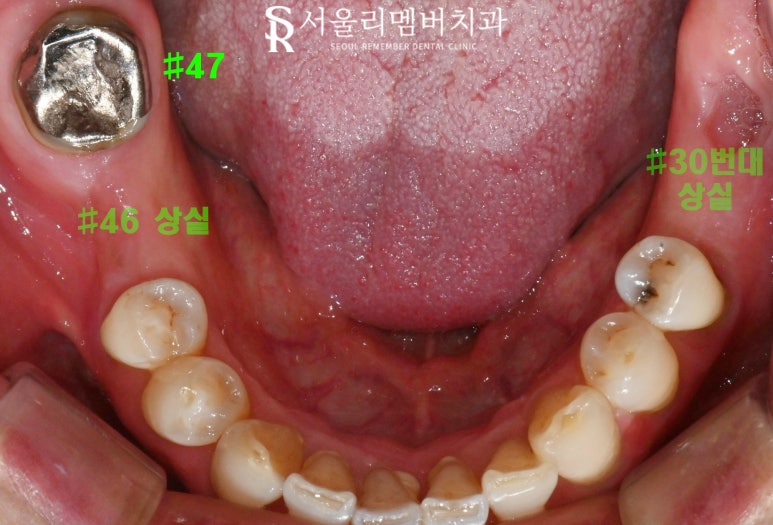

(2) 하악

46번이 없는 상태에서 47번은

배열과 위치가 좋지 않았고,

오래된 보철로 인해 기능이 저하된 것이었습니다.

하악 36번도 손실되었으며,

30번대 구치가 전반적으로 부재한 상황이었습니다.

(3) 전반적 문제

이를 다물었을 때 양측 교합이 불균형한 모습입니다.

또한 치석과 치태가 많이 껴 있어

치주 건강도 좋지 않았습니다.